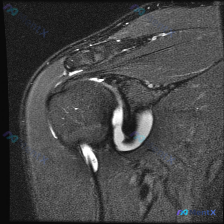

这是一份肩部MRI T2序列冠状位图像,我们先把核心观察点列出来:

- 冈上肌腱:附着于肱骨大结节区域,局部信号显著异常增高,和液体信号强度接近,肌腱连续性在附着点处中断,形态不规则

- 肩峰下-三角肌下滑囊:肩峰下方三角肌之间的间隙,可见明显液性高信号,提示滑囊积液/滑囊炎

- 盂肱关节周围:关节盂唇可见高信号影,提示损伤或变性;关节腔内可见显著高信号积液,分布在关节间隙和下方关节囊;肱骨头骨质形态大致正常,无明确骨髓异常信号或骨折线

和问题直接相关的软组织积液核心发现一共三处:

- 肩峰下-三角肌下滑囊积液

- 盂肱关节腔积液

- 冈上肌腱撕裂口内及周围液体信号,撕裂口和上方肩峰下滑囊相通